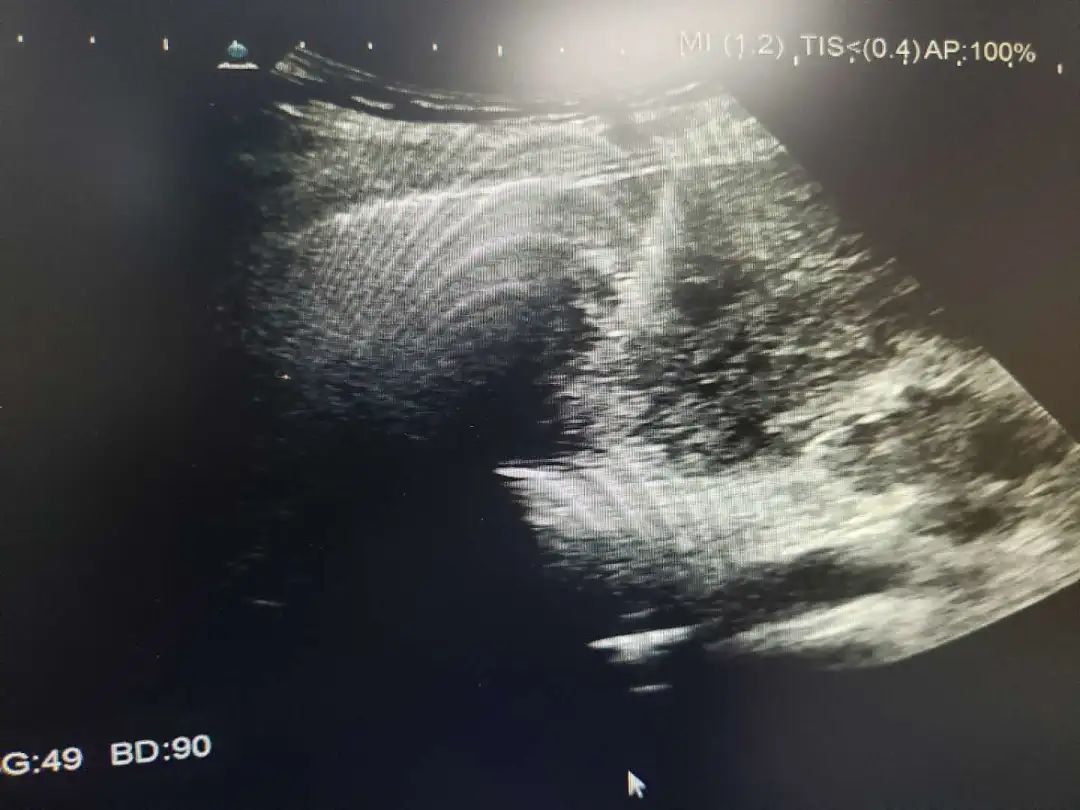

超声引导下肿瘤消融治疗是在实时超声的监视引导下应用专门的治疗针,达到不开刀、对体内的肿瘤原位灭活的一门新技术,其中肝癌经皮微波凝固治疗处国际领先地位。

微波消融治疗肝癌可采用经皮穿刺、开腹手术术中消融或经腹腔镜引导几种方式,超声引导下准确地摆放微波辐射电极,保证凝固坏死区完全覆盖整个肿瘤,达到完全灭活肿瘤。对于小于3厘米的肝癌,射频、微波消融治疗技术成熟,已经取得和手术相同的临床效果,但微创、安全、经济、痛苦小是手术方法无法替代的,尤其是无法耐受手术及复发和转移的肝癌。